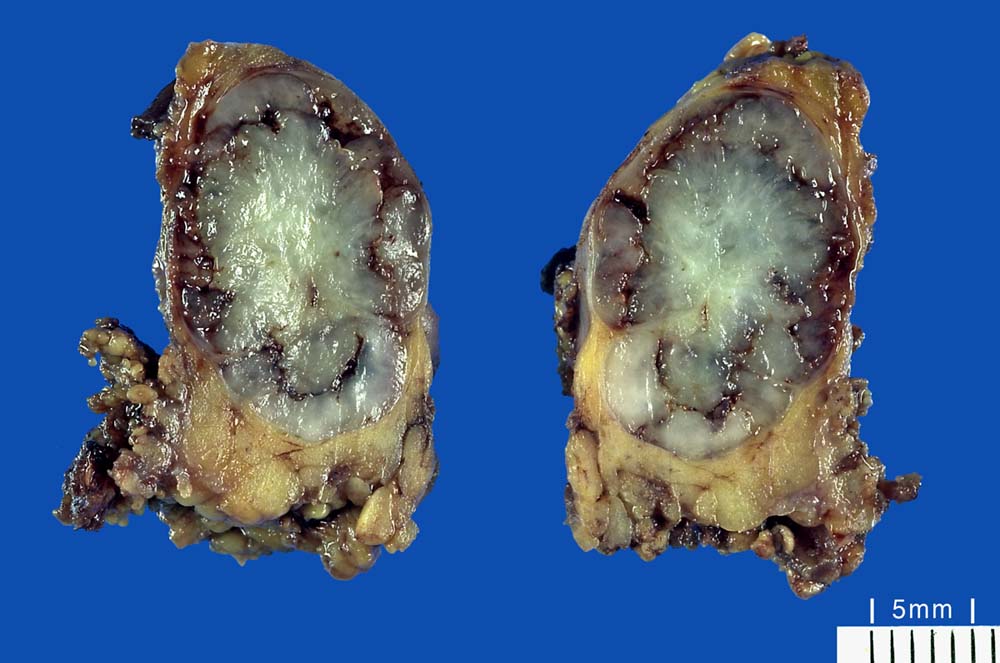

Makroskopie:

Makroskopisch sind pleomorphe Adenome scharf begrenzt. In den grossen Speicheldrüsen sind die meist solitär wachsenden Knoten von einer Kapsel umgeben, nicht aber in den kleinen Speicheldrüsen. Rezidivtumoren bilden oftmals multiple Knoten.

• Scharf begrenzter bekapselter Tumor bestehend aus epithelialen, myoepithelialen und mesenchymalen Anteilen.

• Die stromale Komponente ist teils mukoid, teils hyalinknorplig, teils hyalinisiert bindegewebig.

• Oben im Präparat dem Tumor kappenförmig aufsitzende seromuköse Speicheldrüse (Glandula submandibularis). Das sollte der Kliniker dem Pathologen mitteilen: